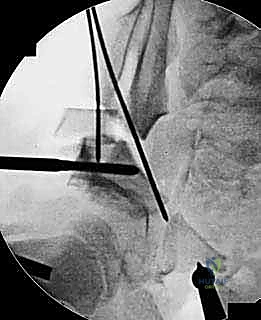

باستخدام أدوات خاصة، يقوم الدكتور هطيف بتدوير التجويف الحقي الحر في ثلاثة أبعاد (للأمام، وللخارج، وللأسفل) حتى يغطي رأس عظم الفخذ بشكل مثالي وميكانيكي سليم. يتم التحقق من الزاوية الجديدة فوراً داخل غرفة العمليات باستخدام جهاز الأشعة السينية المتحرك (C-arm).

5. التثبيت القوي (Fixation)

بمجرد الوصول إلى الوضع المثالي، يتم تثبيت العظام في مكانها الجديد باستخدام براغي معدنية قوية من التيتانيوم أو دبابيس (K-wires). هذا التثبيت يضمن التحام العظام بشكل صحيح خلال فترة التعافي.